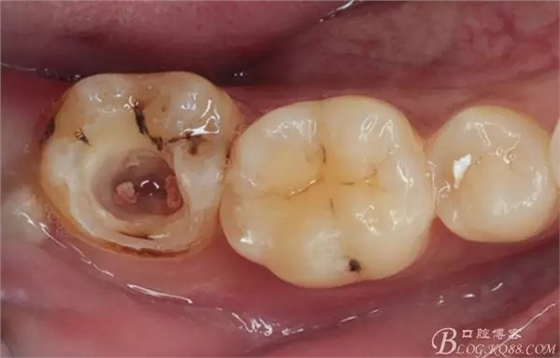

口腔檢查:37頰頜面齲洞,叩(+),探(+),冷熱測試與對照牙對比為敏感。17 27 47 均有不同程度齲壞,無明顯陽性體征。18 28 38 48 呈不同程度傾斜,38 48牙冠部分萌出。全口牙齒排列不整齊,口腔衛(wèi)生較差,牙石(++),部分牙齦發(fā)紅。X線檢查示37牙冠低密度影像累及牙髓,牙周間隙略增寬。

診斷:①37慢性牙髓炎 ②17 27 47頜面齲 ③18 28 38 48阻生牙 ④牙列不齊 ⑤牙齦炎

治療過程:2016-8-16首次處理,含1:100000腎上腺素的2%利多卡因下牙槽神經(jīng)麻醉下行開髓術(shù),初步探及2根管,雙氧+生理鹽水交替沖洗下封VOCO Depulpin多聚甲醛無砷失活劑。